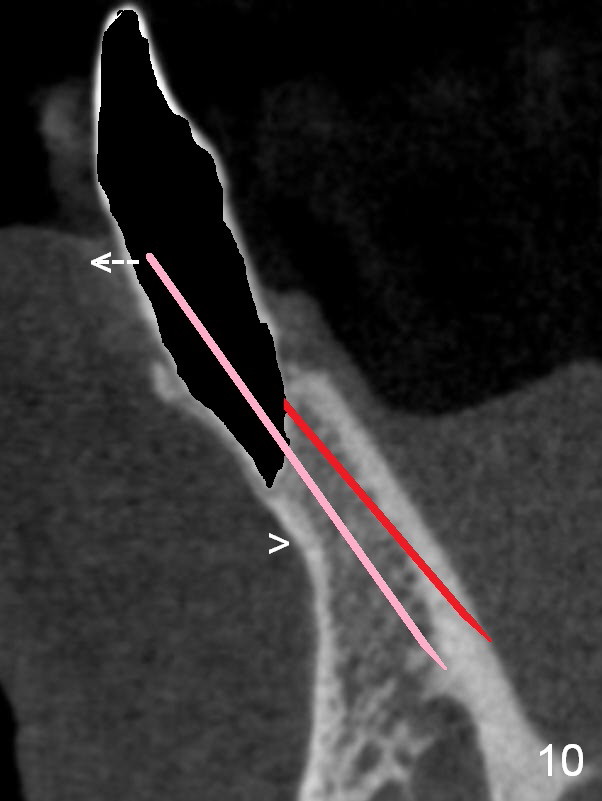

A 74-year-old man has several missing teeth (Fig.1). His 1st goal is to replace the lower left lateral incisor (Fig.2). The residual root has an apical lesion (Fig.3 *). To describe intraop findings, a CT image of a different patient is used (Fig.4 coronal section; B: buccal; L: lingual). After extraction, the buccal plate is found to be thin and low (Fig.5 arrowheads). A 1.5 mm pilot drill (Fig.6 red line) is used to initiate osteotomy in the lingual plate of the socket. Once the drill penetrates the lingual plate, the trajectory changes and the depth is 17 mm from the gingival margin (Fig.7). A PA is taken (Fig.8); it appears that the osteotomy can be extended more apically. When the pilot drill extends to 20 mm, there is sudden empty feeling. The lingual plate has perforated (Fig.9). A new osteotomy is established buccally (Fig.10 pink). To avoid buccal plate perforation, especially in the buccal undercut area (>), the coronal end of the drill has to be tilted buccally (<--). An angled abutment (3x20 mm, 15°) is placed (Fig.11,12). The abutment is modified (Fig.13,14) to accommodate an immediate provisional (Fig.15,16 P). Perio dressing is to be applied to prevent the bone graft from getting dislodged buccally (Fig.15). The dressing is in place 7 days postop (Fig.17).